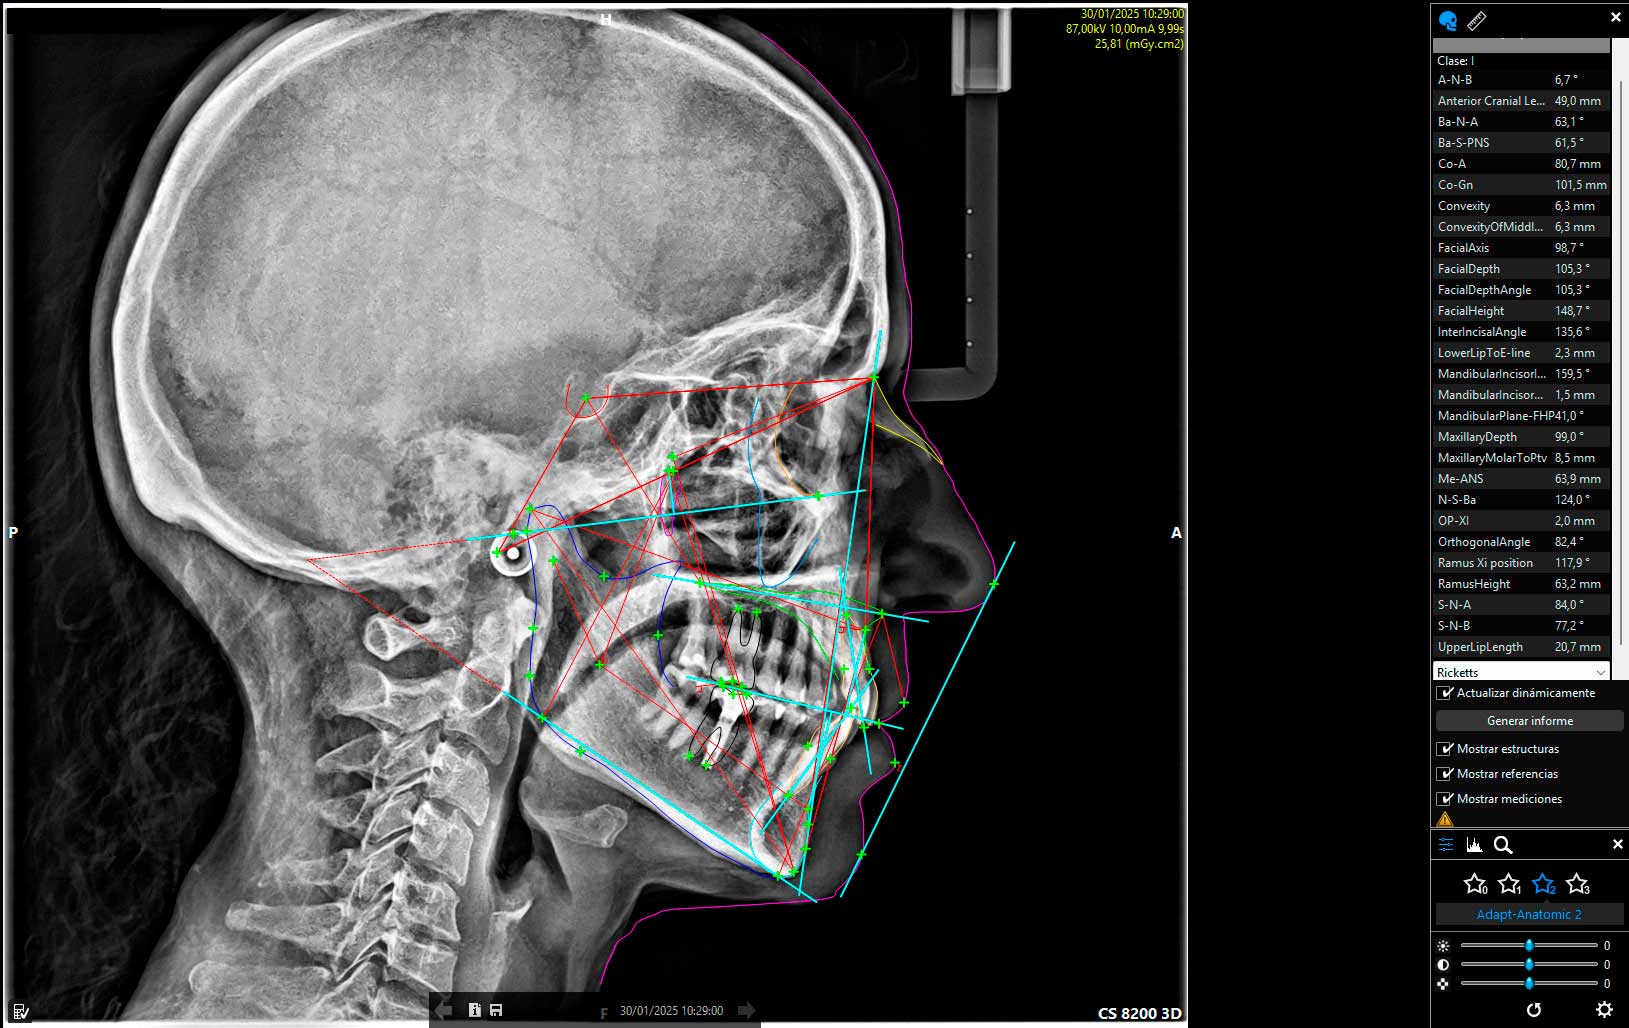

Radiología digital

Reduce en un 80% la radiación que recibe el paciente y permite obtener una imagen de forma instantánea, sin necesidad de revelado. Además, la tecnología digital permite la mejora de la imagen mediante técnicas informáticas. Hemos incorporado además, tecnología 3D mediante un sistema avanzado de Tomografía Computarizada de baja radiación CBCT (la de más baja radiación disponible en el mercado), lo que nos permite determinar la posibilidad de colocación de implantes en la primera visita diagnóstica, así como la detección de patologías asociadas a los maxilares.

Servicio de Tomografía computarizada CBCT, ortopantomografía, telerradiografía y radiografías de ATM al momento

Mediante la radiología digital de baja radiación, podemos valorar estructuras de interés odontológico o craneal, con imágenes 2D o 3D, según sea el caso.